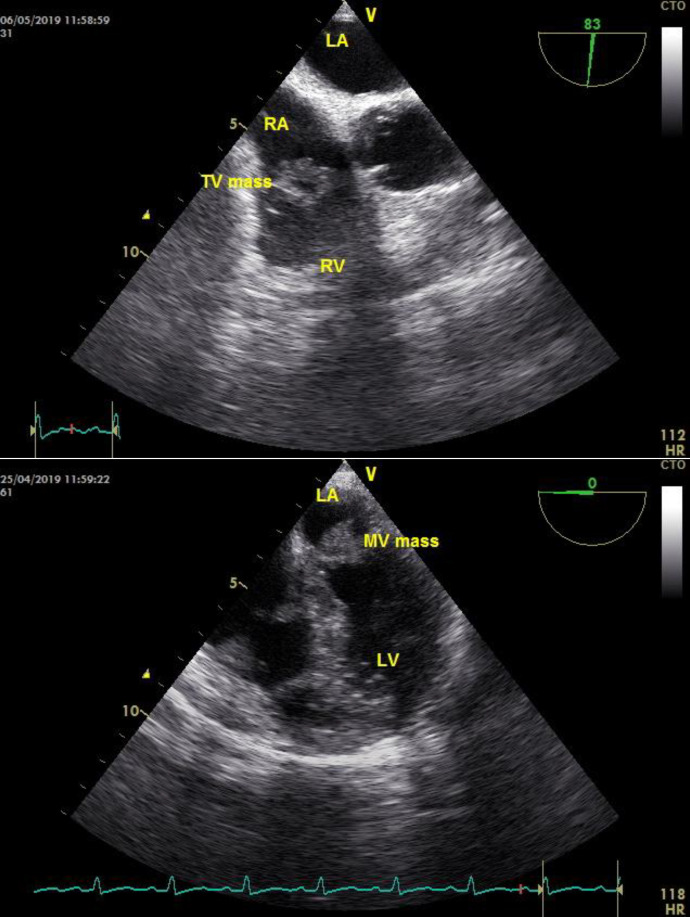

栓塞物质在身体的许多部位形成,可影响身体的任何部位。肺栓塞和栓塞性中风是体内栓塞性疾病最常见的表现形式。栓塞事件有不同的起因,而心脏是栓塞最重要的起源部位之一。非细菌性血栓性心内膜炎(NBTE)是导致栓塞事件的不常见原因之一,可发生在晚期癌症患者身上。NBTE 可导致栓塞。栓塞可能发生在一些器官,包括中枢神经系统、肾脏、脾脏、四肢和冠状动脉。作者旨在描述一例乳腺癌女性患者因非细菌性血栓性心内膜炎(NBTE)并发肺栓塞(PE)和栓塞性中风的罕见病例。

Embolic material forms in many parts of the body and can affect anywhere in the body. Pulmonary embolism and embolic stroke are the most common presentations of embolic disorders in the body. Embolic events have different causes, and the heart is one of the most important places where emboli originate. One of the uncommon causes of embolic events is non-bacterial thrombotic endocarditis (NBTE), which can occur in patients with advanced cancer. NBTE can lead to embolism. Embolisation may occur in some organs including the central nervous system, kidneys, spleen, limb extremities, and coronary arteries. The authors aim to describe a rare case with concurrent pulmonary embolism (PE) and embolic stroke caused by non-bacterial thrombotic endocarditis (NBTE) in a woman with breast cancer.